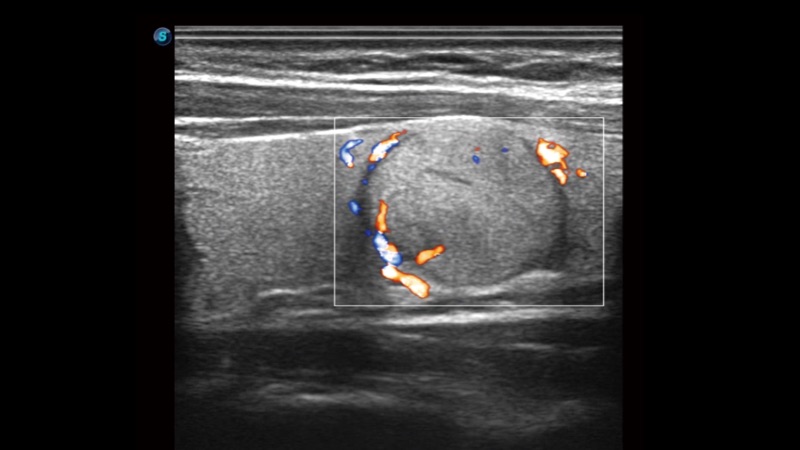

開立醫(yī)療通過不斷的技術(shù)創(chuàng)新,為大眾的生命健康提供持續(xù)關(guān)愛。P12 Plus采用全新一代超聲成像平臺,新平臺旨在將真實(shí)還原組織解剖結(jié)構(gòu)作為首要目標(biāo)。平臺采用全新集成化硬件模塊,搭載新一代芯片,系統(tǒng)性能得到大幅提升,為您的診斷提供了豐富的臨床信息。優(yōu)異的圖像表現(xiàn),豐富的探頭配置,全面的應(yīng)用功能,為您日常診斷提供了可靠的助手。

P12 Plus

彩色多普勒超聲診斷系統(tǒng)